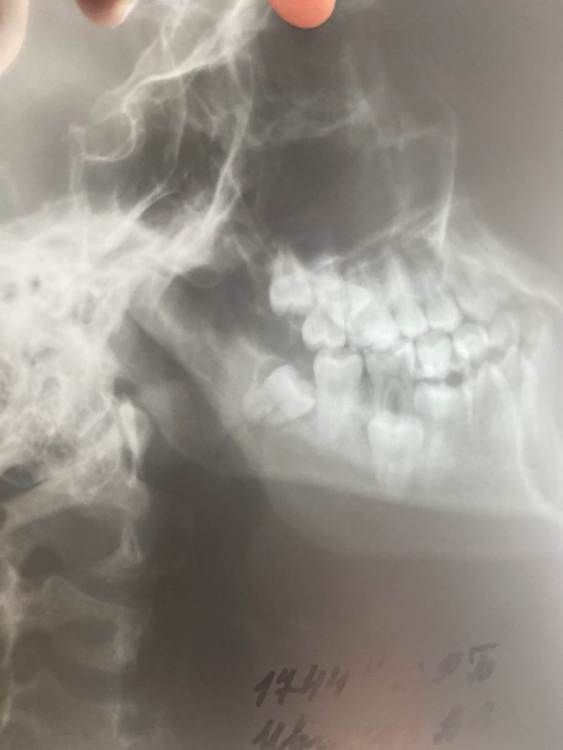

Taipan Опубликовано 25 апреля, 2021 Поделиться Опубликовано 25 апреля, 2021 (изменено) Здравствуйте, 04.04.2021 сломали челюсть в области правого нижнего угла, неделю ходил, думал ушиб, по итогу сделал снимки и вот - перелом, без обломков и смещения. Наложили шину Васильева 12.04, сказали ходить 21 день, после шины онемел подбородок и губа. 23.04 от шины начали болеть зубы, 2 нижних вылезли и деформировались, снял с передних зубов резинки, тк они их очень сильно тянули, 24.04 начал снимать резинки и кушать легкопережовывающу пишу, после еды одеваю обратно резинки, половина зубов на нижней челюсти( со стороны перелома) как будто онимели. Подскажите пожалуйста, что это за онемение и можео ли снимать резинки на пол часа и кушать ? Изменено 25 апреля, 2021 пользователем Taipan Дополнял информацию Ссылка на комментарий

Irouil Опубликовано 27 апреля, 2021 Поделиться Опубликовано 27 апреля, 2021 Да, сейчас гораздо лучше, спасибо Перелом формально со смещением, но оно минимальное. Стандартный срок ношения иммобилизации - 28 дней, затем обычно проводятся контрольные снимки для оценки состояния костной мозоли. То, что Вы нерегулярно носили тракции (резинки) и пострадали зубы - не очень хорошо, но главный показатель в таких ситуациях - болевая симптоматика. Есть простой тест, при полностью закрытом рте надавить немного на подбородок спереди назад. Если при надавливании ничего в области перелома не болит - значит все в порядке, заживление идёт нормально. Ссылка на комментарий